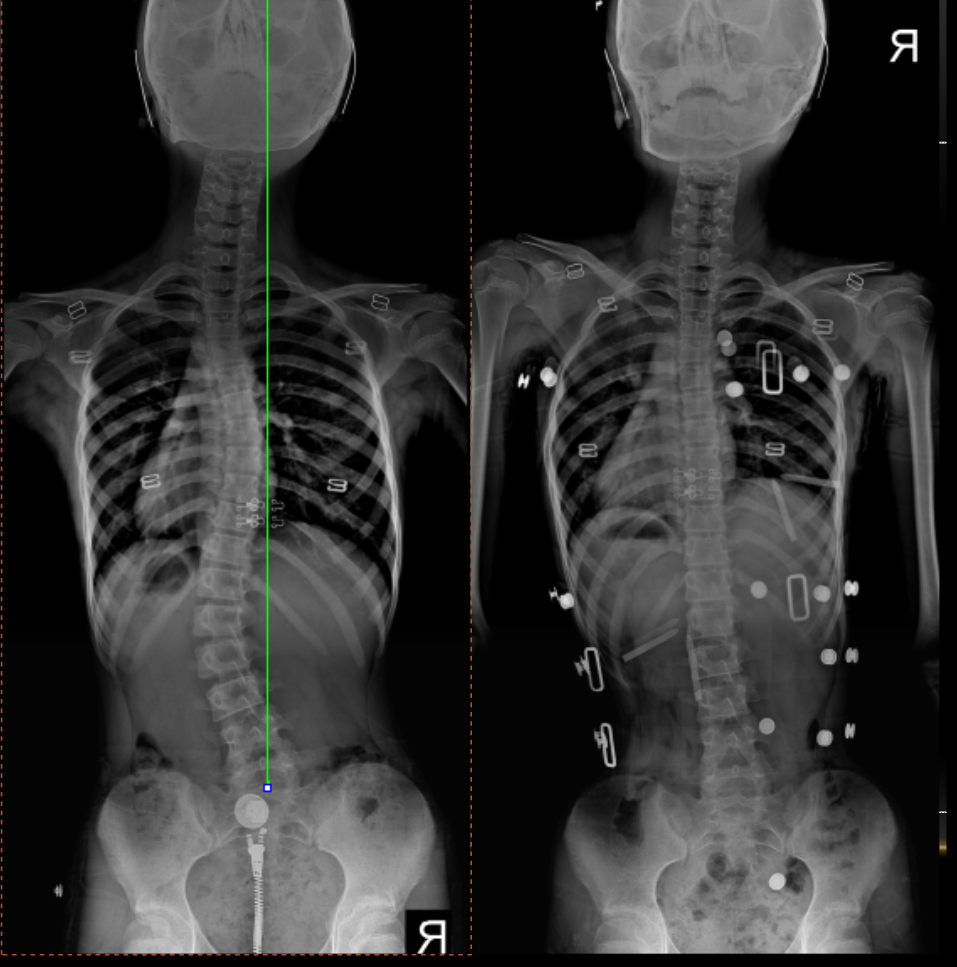

However, when spinal deformity becomes severe, it can lead to compression

of internal organs (viscera) and, in extreme cases, may impact overall

health and life expectancy.

Idiopathic scoliosis accounts for approximately 80–90% of all cases,

meaning no specific underlying cause is identified.

10–20% of cases have a known etiology, including:

Congenital

scoliosis

Neuromuscular or

neuropathic conditions